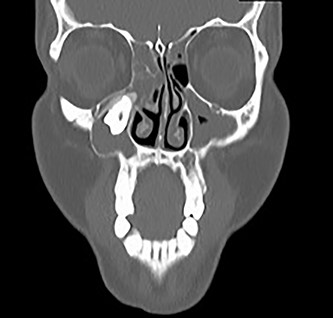

A 29-year-old female patient was referred from the Maxillofacial surgeons to ENT outpatients, for assessment of a loose upper right molar and right-sided retro-orbital pain, ongoing for 4 months. She had no past medical or surgical history and was a lifelong non-smoker with no significant family history. Imaging with a orthopantomogram (Fig. 1) depicted an ectopic tooth in the right maxillary sinus. CT imaging further characterized a thin-walled cystic mass in the right maxillary sinus (Figs 2 and 3), and opacification of the maxillary and ethmoidal air cells is also visualized alongside the afore mentioned ectopic tooth.

Coronal CT image of the right ectopic tooth at the antrum of the right maxillary sinus.